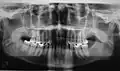

Radiografía intrabucal

La radiografía intrabucal es una técnica exploratoria consistente en la colocación, dentro de la boca, de placas radiográficas de diferente tamaño que son impresionadas, desde el exterior, por un aparato de rayos X.

Es imprescindible que todo profesional tenga conocimientos para realizar este tipo de proyecciones de forma aceptable y esté capacitado para su lectura e interpretación. Son, por tanto, en su ejecución e interpretación, del total dominio del odontólogo o del estomatólogo. Únicamente el empleo de una técnica radiográfica llevada a cabo con precisión aporta radiografías intrabucales interpretables. Las técnicas intrabucales se utilizan preferentemente para diagnósticos dentarios y peridentarios, aunque muchas veces son una ayuda muy valiosa para matizar ciertos detalles en estudios más amplios del macizo maxilofacial. Destaca la utilización en cirugía bucal de las técnicas de desplazamiento, horizontales o verticales, para la localización anatómica de dientes retenidos o cuerpos extraños, y la obtención de imágenes con gran definición de zonas concretas que facilitan la realización de un diagnóstico. También se usa la radiografía intrabucal en la valoración de la osteointegración de los implantes intraóseos.

Su nombre, radiografía intrabucal, se debe, naturalmente, a que las películas se colocan dentro de la cavidad bucal. Según el tamaño y la colocación de las películas, se pueden clasificar en procedimientos periapicales o retroalveolares, interproximales o de aleta mordida y oclusales. Un requisito imprescindible previo para la realización de la radiografía intrabucal es retirar prótesis metálicas removibles, dispositivos ortodóncicos o cualquier objeto metálico que se encuentre en el área a estudiar. Además, es necesaria la inmovilización perfecta de la cabeza del paciente en la posición idónea.

- Las técnicas periapicales o dentoalveolares, sirven para explorar el diente en su totalidad, desde la corona hasta el ápice, el espacio periodontal y el tejido óseo que lo rodea. Se puede realizar mediante dos procedimientos: la técnica de bisectriz y la de planos paralelos.

Radiografía intrabucal: técnicas interproximales o de aleta mordida

- Las técnicas interproximales o de aleta mordida son muy útiles para el estudio sistemático y la exploración de la caries dental. Se aprecian caries interproximales y oclusales, pero también alteraciones pulpares, restauraciones desbordantes, recidivas de caries bajo éstas, ajustes de prótesis fijas, cresta alveolar, límite amelocementario…en una misma película se observan las regiones coronal y cervical de los dientes superiores e inferiores a la vez. El examen es cómodo y rápido, ya que las películas no se clavan en el suelo bucal; por este motivo es una exploración habitual para la detección de caries interproximales en niños.

Radiografía intrabucal: técnicas oclusales

- Las técnicas oclusales se denominan así porque la colocación y sujeción de la película se realizan en el plano oclusal, entre el maxilar y la mandíbula, dirigiéndose el haz de rayos desde arriba o desde abajo, perpendicular u oblicuamente. Se utilizan como complemento de los procedimientos periapicales, para estudios más amplios de áreas óseas, fracturas alveolares, palatinas o del cuerpo mandibular, límites de lesiones quísticas o tumorales, dientes incluidos y cuerpos extraños.